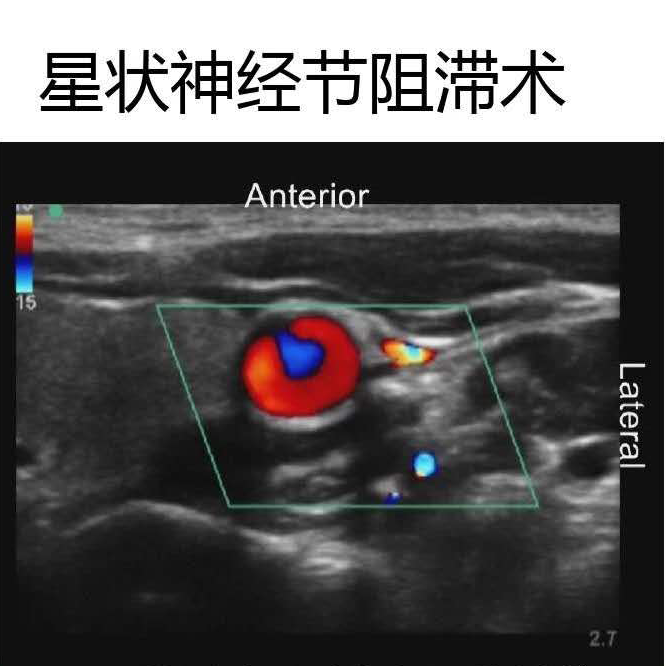

如星狀神經(jīng)節(jié)阻滯術(shù)

圖片8.png